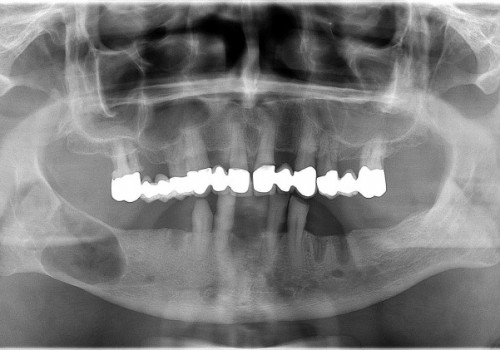

İnkşafı və böyüməsi tədricən baş verdiyindən, bu proses pasiyent tərəfindən demək olar ki hiss edilmir. Yalnız törəmənin ciddi ölçülərə çatması nəticəsində və ya iltihablanması nəticəsində meydana çıxan kliniki əlamətlər nəticəsində aşkarlanır. Əksər hallarda isə çəkilən diş və çənə rentgen şəkillərində təsadüfən rast gəlinir.